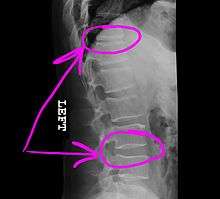

Today, the telestrator is used in a wide variety of applications (from educational, boardroom, church and military presentations to telemedicine conferences), where it can be used by both the near and far ends to annotate precise details of microscopic images or other medical images that are under consultation. The telestrator is also used in courtrooms to communicate details of multi-media images presented to a jury, as was most famously seen during the O.J. Simpson trial in March 1995.[2]

Example of how a telestrator might annotate a medical image shared during a telemedicine session. Image courtesy of Boeckeler Pointmaker.